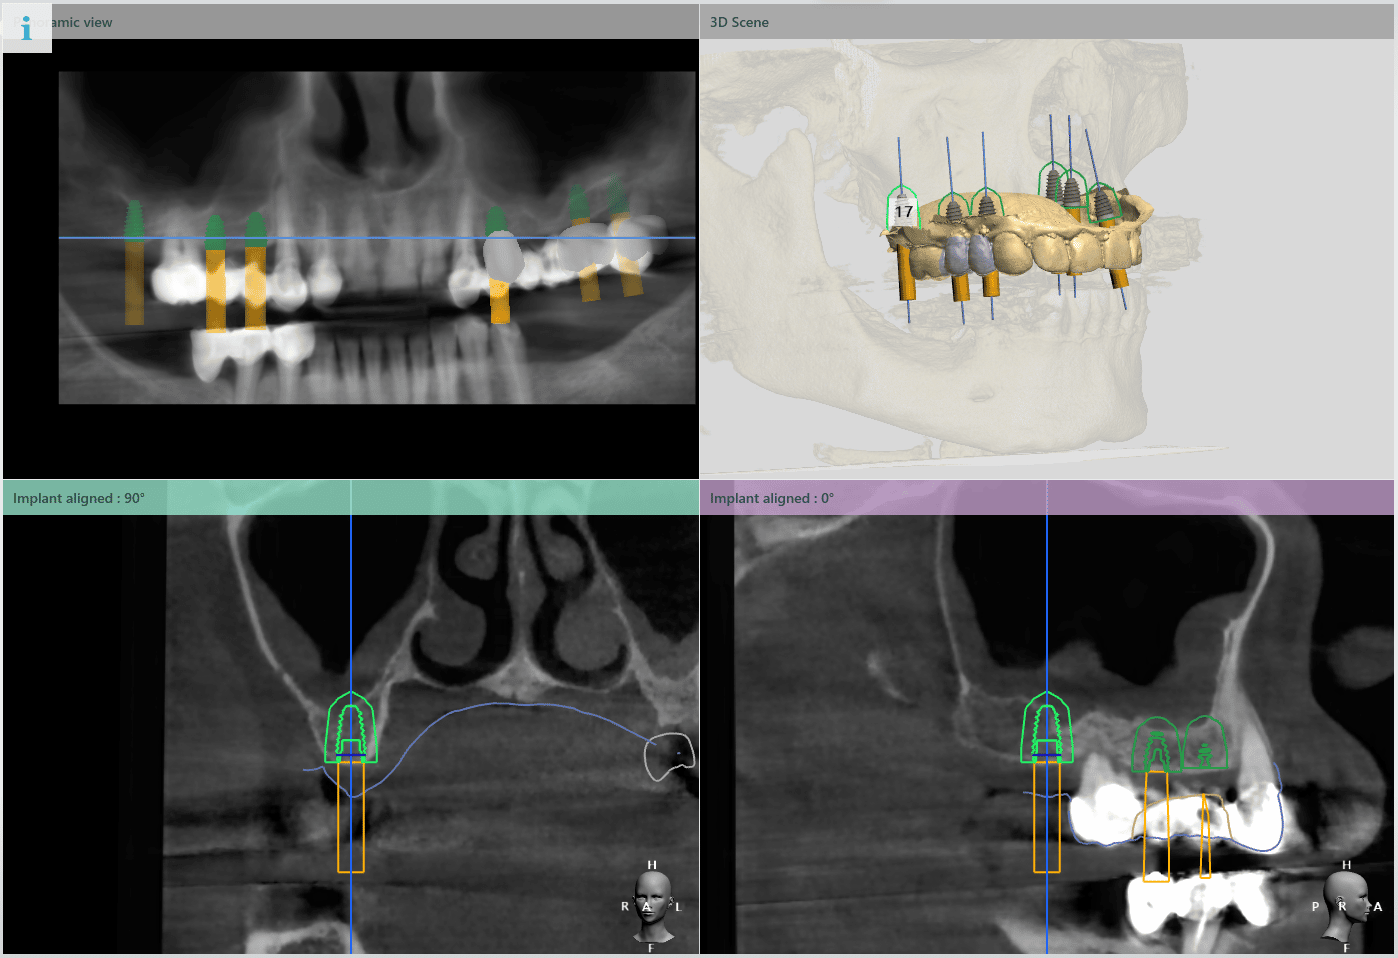

În urma evaluării CBCT-ului s-a constatat necesitatea realizării augmentarii osoase ăn zona posterioară maxilară, lifting sinusal maxilar bilateral odată cu inserarea implanturilor.

Pentru a se asigura că implanturile dentare vor fi plasate în poziția ideală din punct de vedere estetic și funcțional, medical implantolog a recomandat inserarea implanturilor dentare cu ajutorul ghidului chirurgical.

Medicul specialist a efactuat scanarea digitală a arcadelor pe care a trimis-o tehnicianului dentar DigiRay, împreună cu CBCT-ul pacientului.

Odată planficată și agreată poziția și axul de inserție al fiecarui implant, tehnicianul DigiRay efectuează designul șablonului chirurgical și printarea acestuia dintr-o rășină bio-compatibilă.